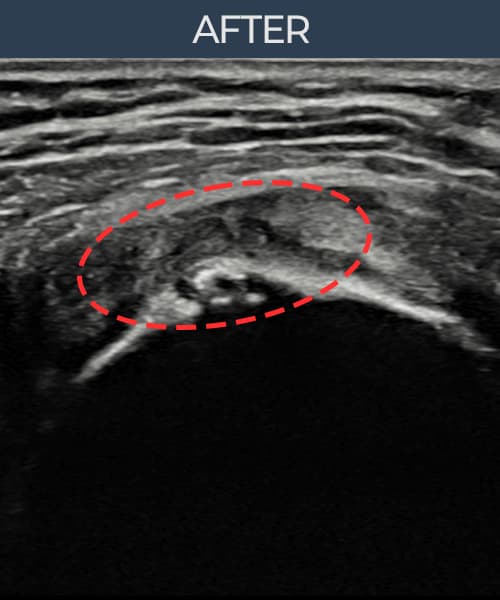

실제 환자의 시술 전후 초음파 영상입니다.

수술 없이 이뤄낸 회복을 직접 확인하세요.

모든 초음파 영상은 실제 환자의 동의를 받아 게시하였습니다. 개인차가 있으며 동일한 결과를 보장하지 않습니다.

[촬영시기:23.07.18~23.09.14]

[어깨인대 축소봉합술] 좌측 어깨 광범위 파열로 수술을 권유받았으나 비수술 치료를 원해 내원하셨습니다.